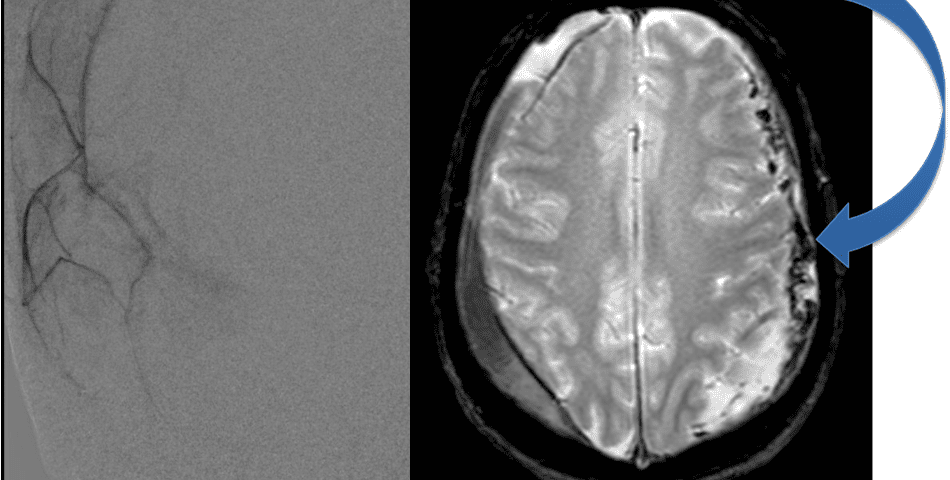

CT follow-up at 1 week demonstrates early resorption. 2 weeks post MMA embolization, resolution of the left subdural collection with new small thin acute hemorrhage in an otherwise stable right subdural collection is observed (Figure 3. A and B).

Figure 3. A) 1 week post MMA embolization demonstrating decreasing thickness bilaterally B) 2 weeks post MMA demonstrates resolution on left, with small new acute component on right with overall decreased thickness.

Clinically, the patient improved over the few weeks with the occasional transient twinge of a headache, but resolution of dizziness. Follow-up CT at 10 weeks demonstrated complete resolution of the bilateral subdural hematomas with our patient completely asymptomatic and back to all of her activities of daily living. Considering her history of thrombocytopenia and CLL, we will continue to monitor her into the future and are excited about her progress and recovery. (Figure 4. A and B)

Figure 4. A and B) – 10 weeks following embolization demonstrates complete resolution of bilateral collections both acute and chronic.